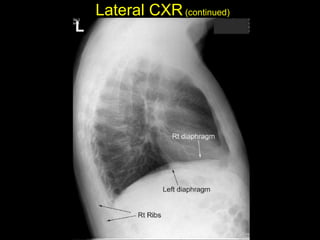

The document discusses the anatomy of the chest x-ray and CT scan by describing the lobes of the lungs and their locations. It also mentions the heart, mediastinum, hilum, and ribs. Several axial, coronal, and sagittal CT images are included with labels pointing out structures like the trachea, bronchi, lobes of the lungs, and fissures. In summary, the document provides an overview of lung and chest anatomy as seen on x-rays and CT scans through text descriptions and labeled medical images.